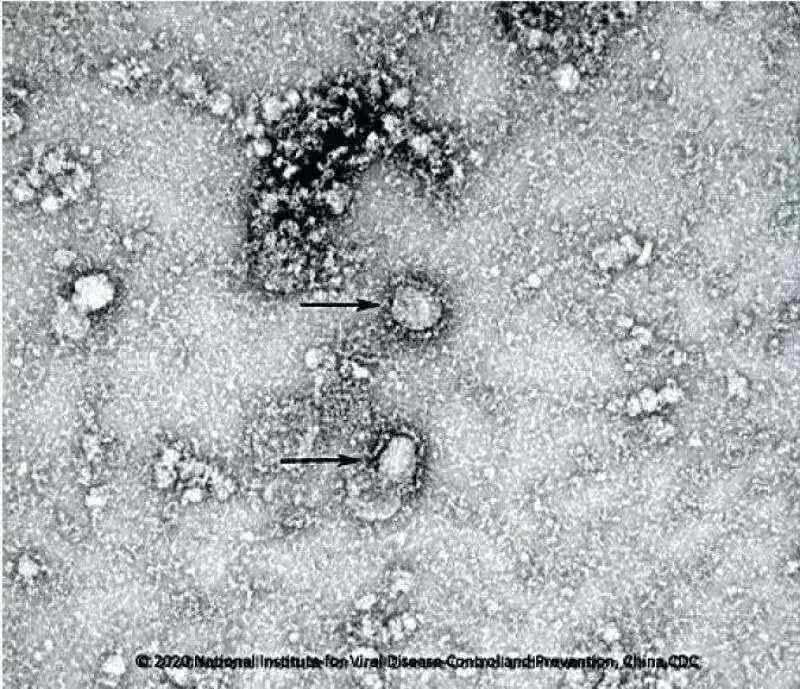

图丨1月24日,国家病原微生物资源库发布了由中国疾病预防控制中心病毒病预防控制所成功分离的我国第一株病毒毒种信息及其电镜照片、新型冠状病毒核酸检测引物和探针序列等国内首次发布的重要权威信息,并提供共享服务(来源:中国疾病预防控制中心病毒病预防控制所)